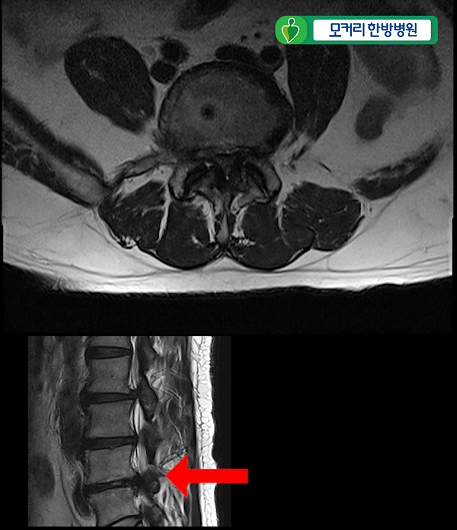

<4-5번>

이 환자분은 협착증을 25년간 앓으시고 증상도 매우 심하신 환자분입니다.

허리 세 마디 2번 3번, 3번 4번, 4번 5번, 이렇게 세 마디의 척추관이 심하게 막혀 있습니다.